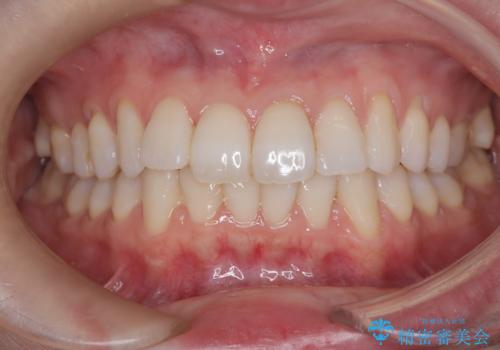

インビザラインモデレートによる前歯の叢生改善|IPR最小限で自然な歯並びへ

前歯の叢生は解消され、自然で調和の取れた歯並びが得られました。

「歯をほとんど削らずにきれいになった」と、患者様にもご満足いただけました。